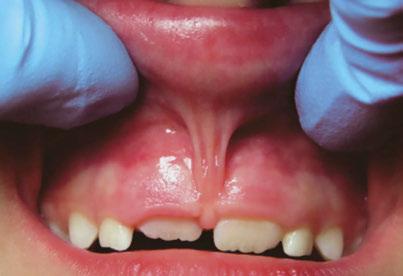

An 8-year-old Hispanic male presented to our private practice in Miami, Florida with the chief complaint of a missing front tooth (Figure 1). Upon review of his medical history, the mother revealed that her son had Autism Spectrum Disorder and confirmed that his condition was severe. This patient did not take

12 Orthodontic Practice US Volume 14 Number 2 CLINICAL

Figure 1: Face of 8-year-old patient at initial consultation

any medications, was nonverbal, avoided eye contact with any staff member including the treating pediatric dentist, did not sit in the dental chair, and was constantly tapping his ears. No dental radiographs were obtained due to his uncooperative behavior. For the dental exam, the mother agreed and consented with placing him in a passive restraining device. With a limited visualization of his oral cavity, a mixed dentition was noted. The maxillary right permanent central incisor was absent. No significant pathology was found in his oral soft tissues. Dental caries was found on both primary and permanent molars. A decision was made to complete dental treatment using general anesthesia as a behavior management technique at the local children’s hospital.